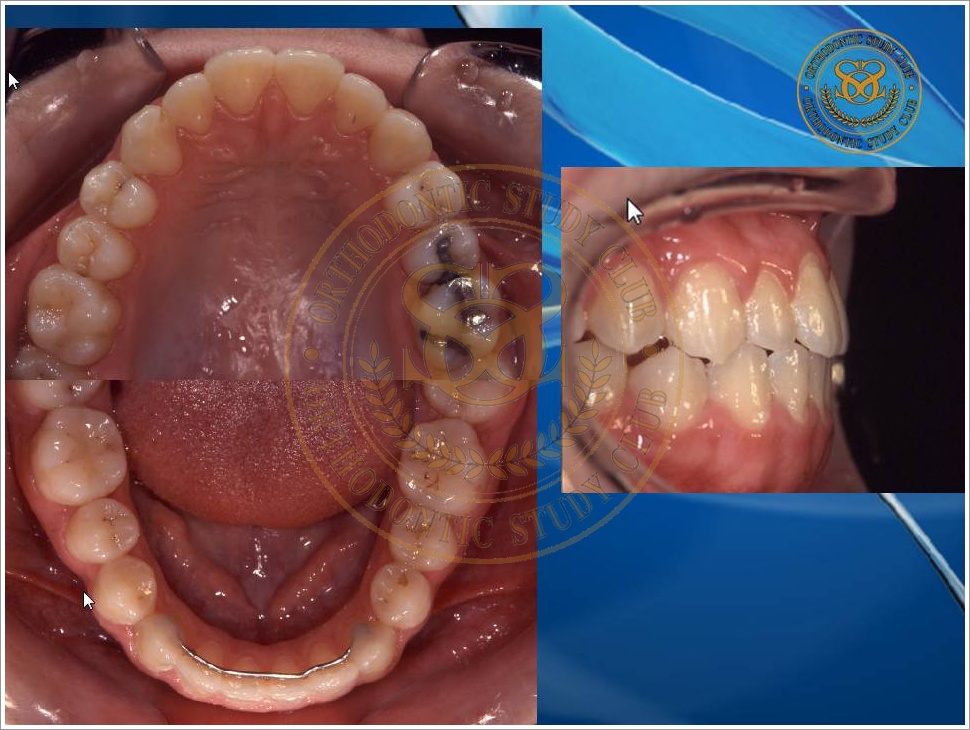

Treatment of Pseudo Class III (Class I Molar Relationship) and management of the embedded maxillary canine (Pt. Miss J.I.)